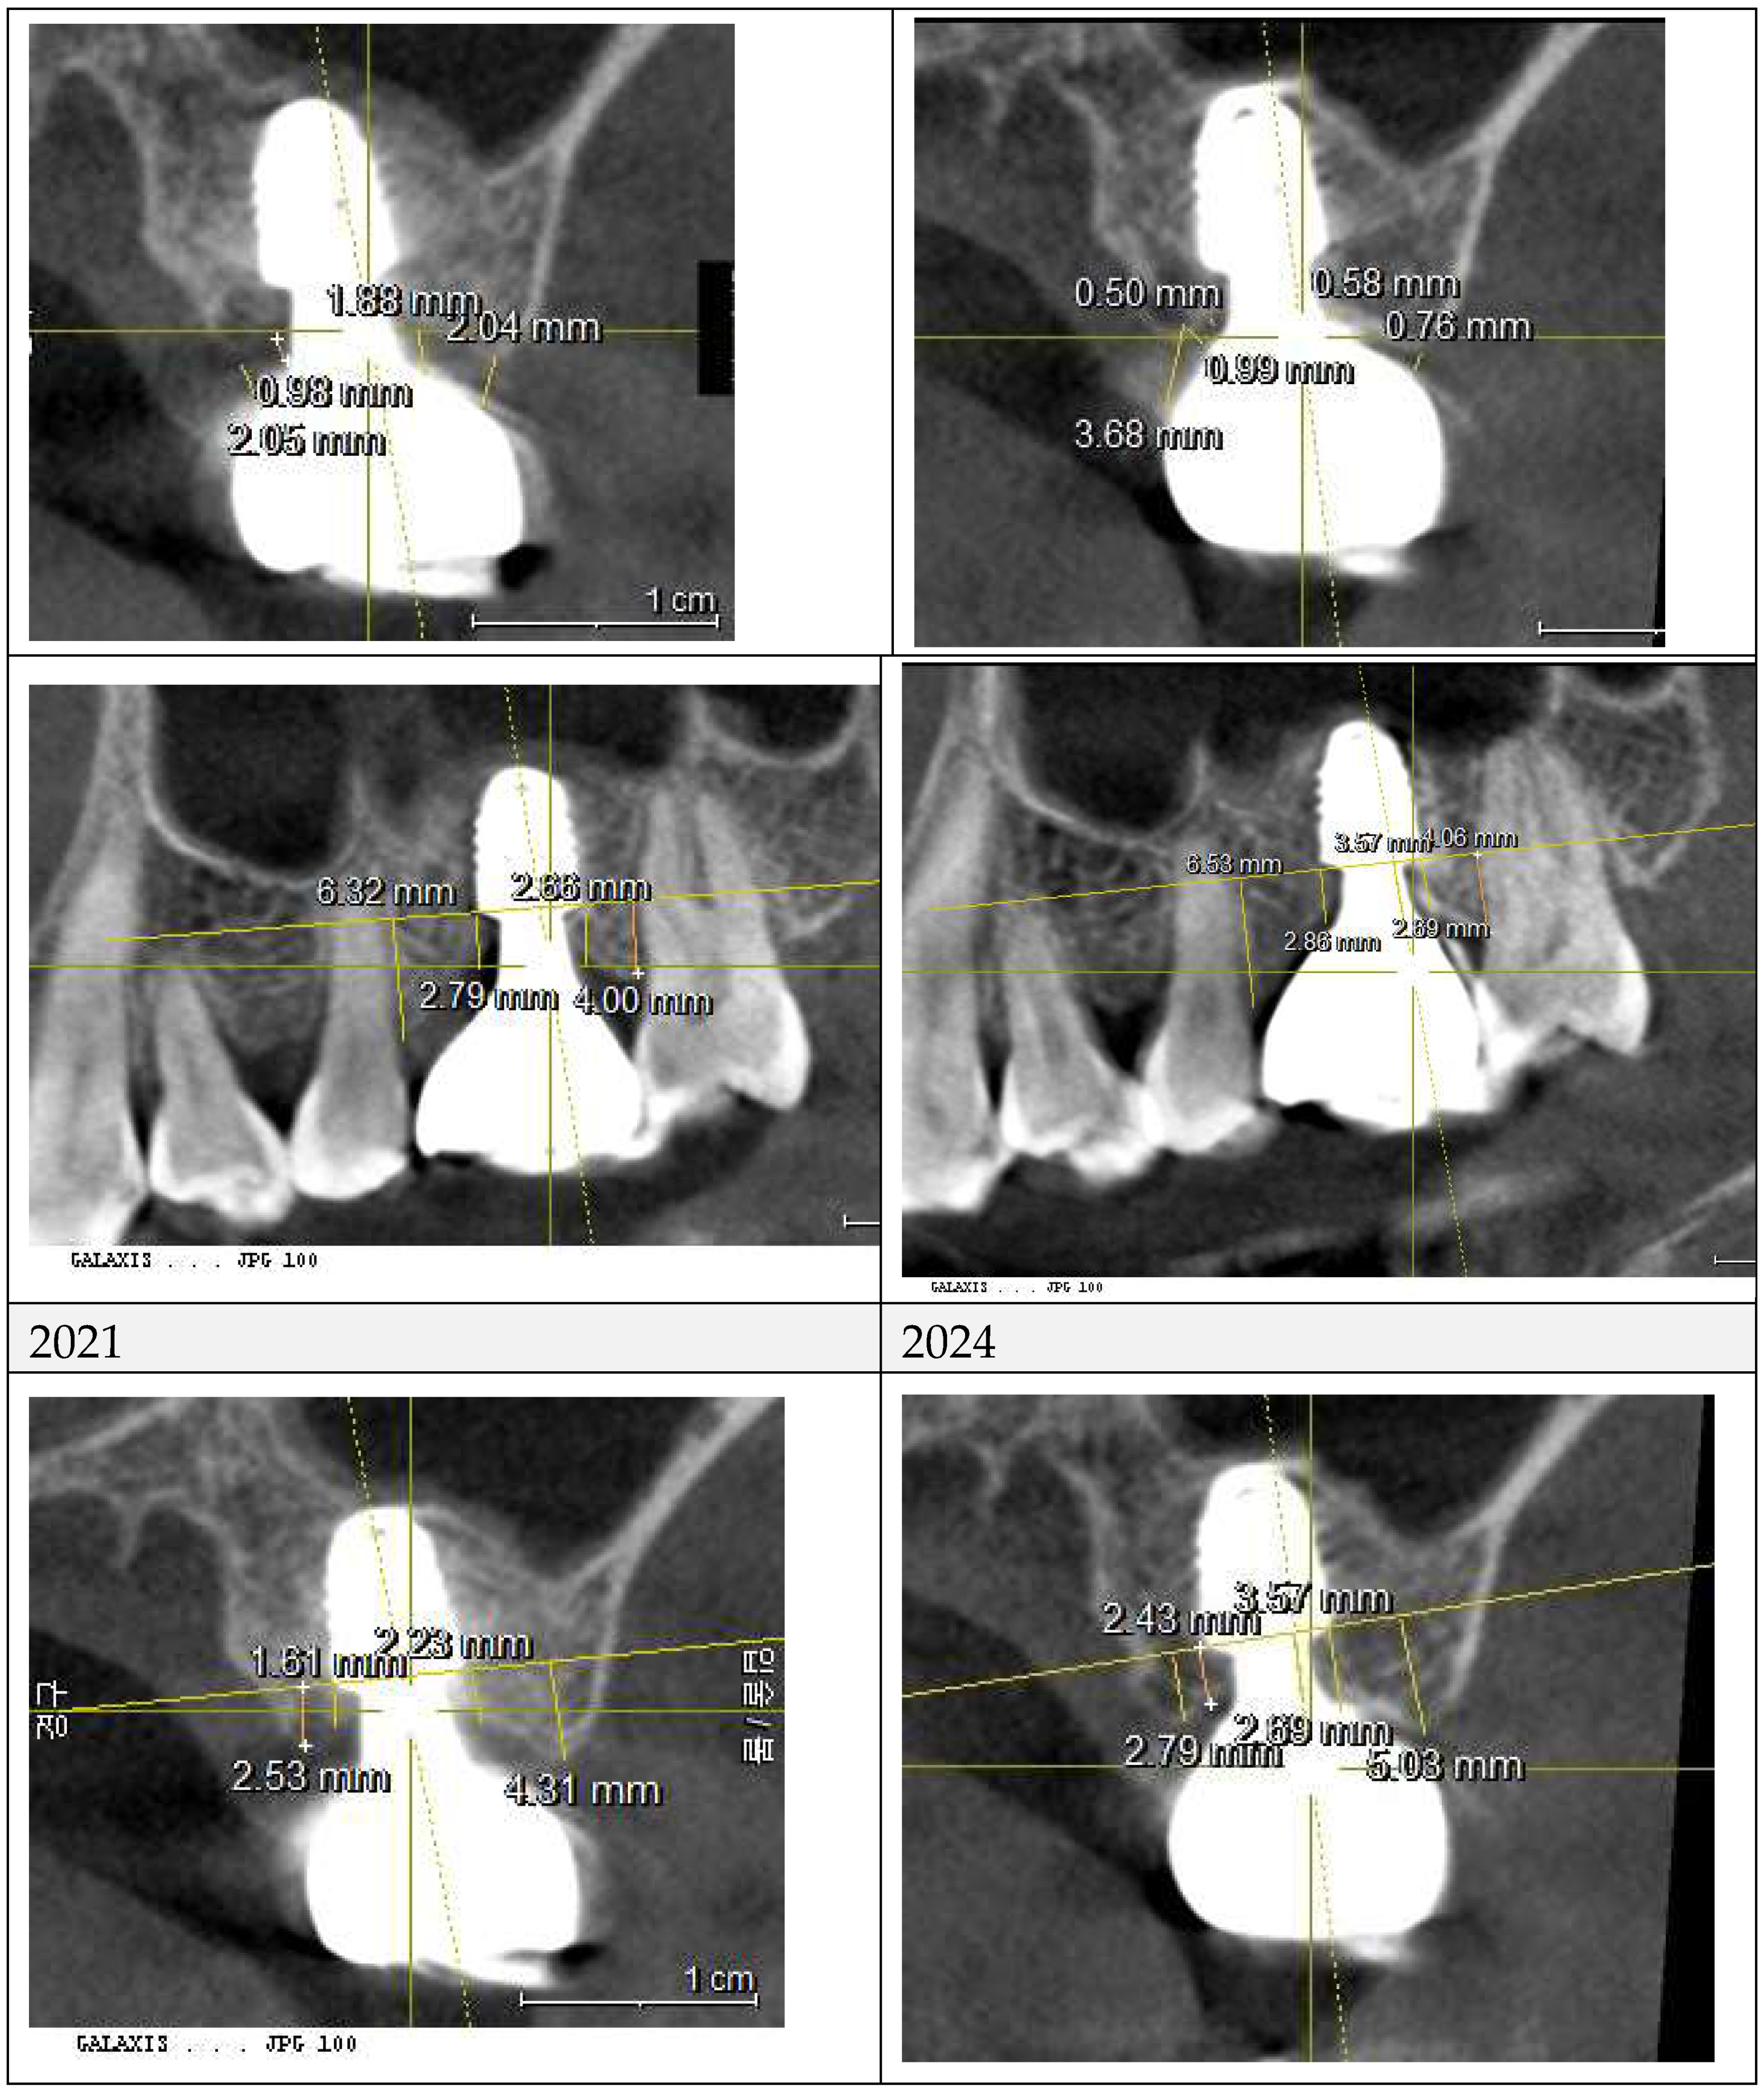

Figure 7 and

Figure 8 illustrate the radiographic changes observed from 2021 to 2024 at the lower right first molar implant site (control site) and the upper left first molar implant site (experimental site), respectively. (

Figure 7,

Figure 7.

This image illustrates the X-ray measurements conducted on the lower right first molar implant, comparing data from 2021 and 2024.

Figure 8.

This image illustrates the X-ray measurements conducted on the upper left first molar implant, comparing data from 2021 and 2024.

Figure 10 compares X-rays from October 2021 and July 2024, showing a marked decrease in Crest to Restoration Distance (CRD) after restoration modification. (

Figure 10) The reduction ensured the gap was fully occupied by peri-implant soft tissue, eliminating voids. This suggests that maintaining CRD within a critical range is essential for a stable biological seal, reinforcing the soft tissue barrier against bacterial infiltration.